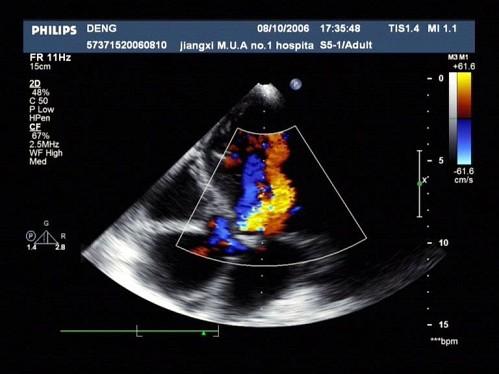

彩超跟B超的區(qū)別,是在其基礎(chǔ)上增加了多普勒功能。多普勒功能指的是通過運(yùn)用相關(guān)技術(shù),將獲得的血流信號處理并疊加在B超圖像上,使我們看到紅色或藍(lán)色的血流,讓我們判斷血液流動的情況。

就像我們平時對著一根水管拍照,單純使用B超的話,我們只能在照片里看到它的外形;若加上多普勒功能,我們就能看到水管里的水是往哪邊流了。